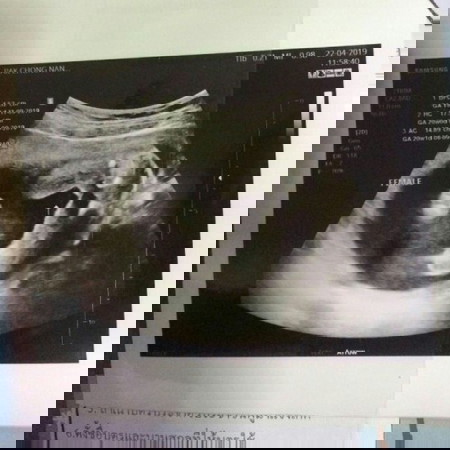

ซาวตอน 21w 4d จ้า หมอบอกได้ผู้หญิง แต่หมอที่นี้เคยมีประวัติซาวผิดบ่อย ขอคนดูเป็นคอนเฟริมน่อยจ้าา